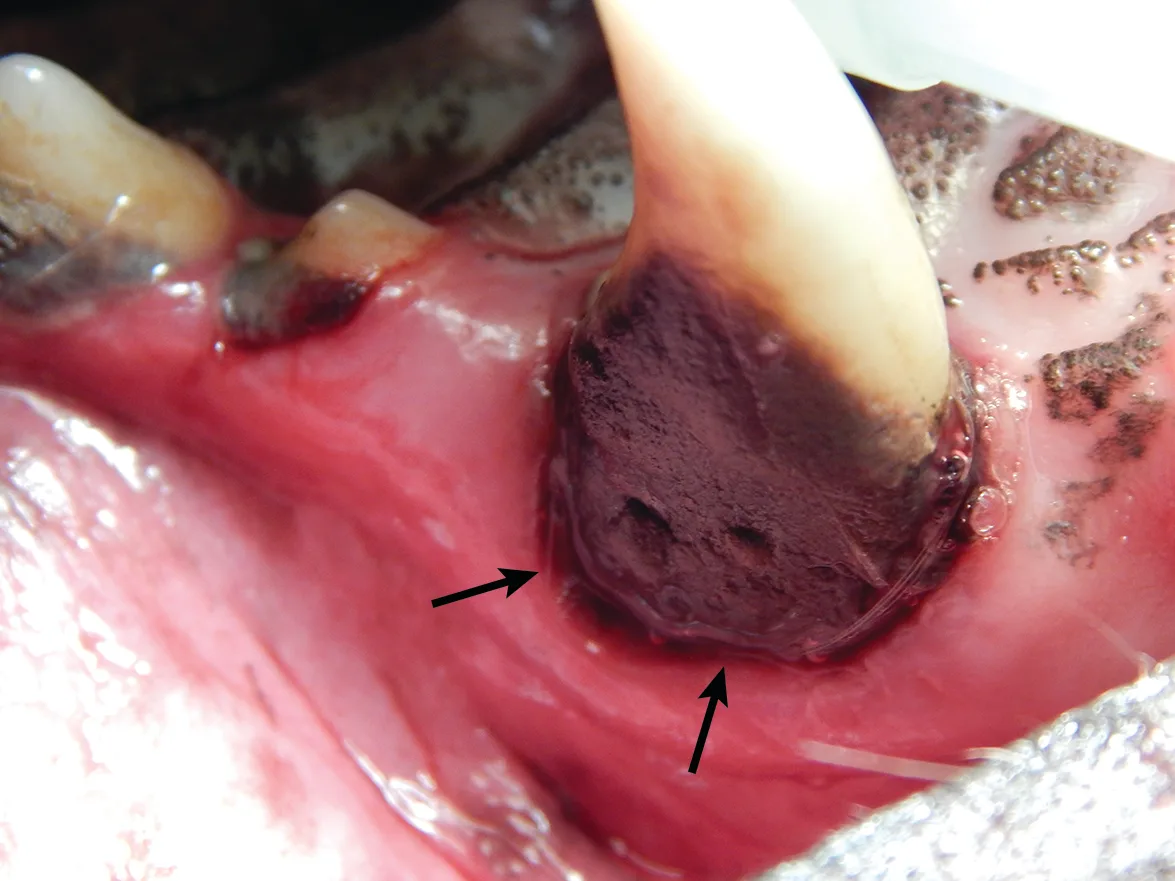

3. Jaw Fracture

Iatrogenic fracture of the jaw can be a serious complication of surgical extractions and is most commonly associated with surgical extraction of mandibular canine teeth in dogs and cats and mandibular first molar teeth in dogs (Figure 10). These extractions can be difficult to perform, as the root apexes are often located in close proximity to the ventral cortex of the mandible, possibly leading to significant bone loss when severe disease is present and increasing the risk for iatrogenic fracture (Figure 11).

Pathologic fracture (arrow) secondary to severe periodontal disease of the right mandibular first molar tooth in a dog